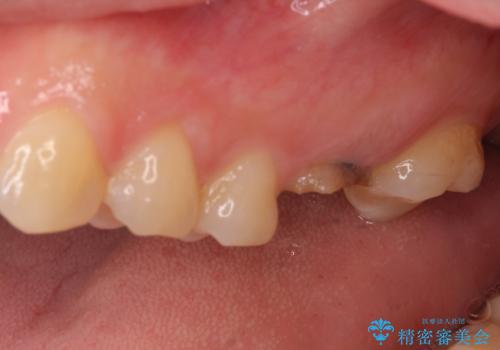

- 抜歯が必要と診断された奥歯を気にして来院された患者様です。

抜歯の上インプラントによる補綴治療を行うこととなりましたが、前歯の叢生も気になるとのことで並行して矯正治療を行うこととしました。

前歯のデコボコも解消され、ブラッシングが楽になりました。